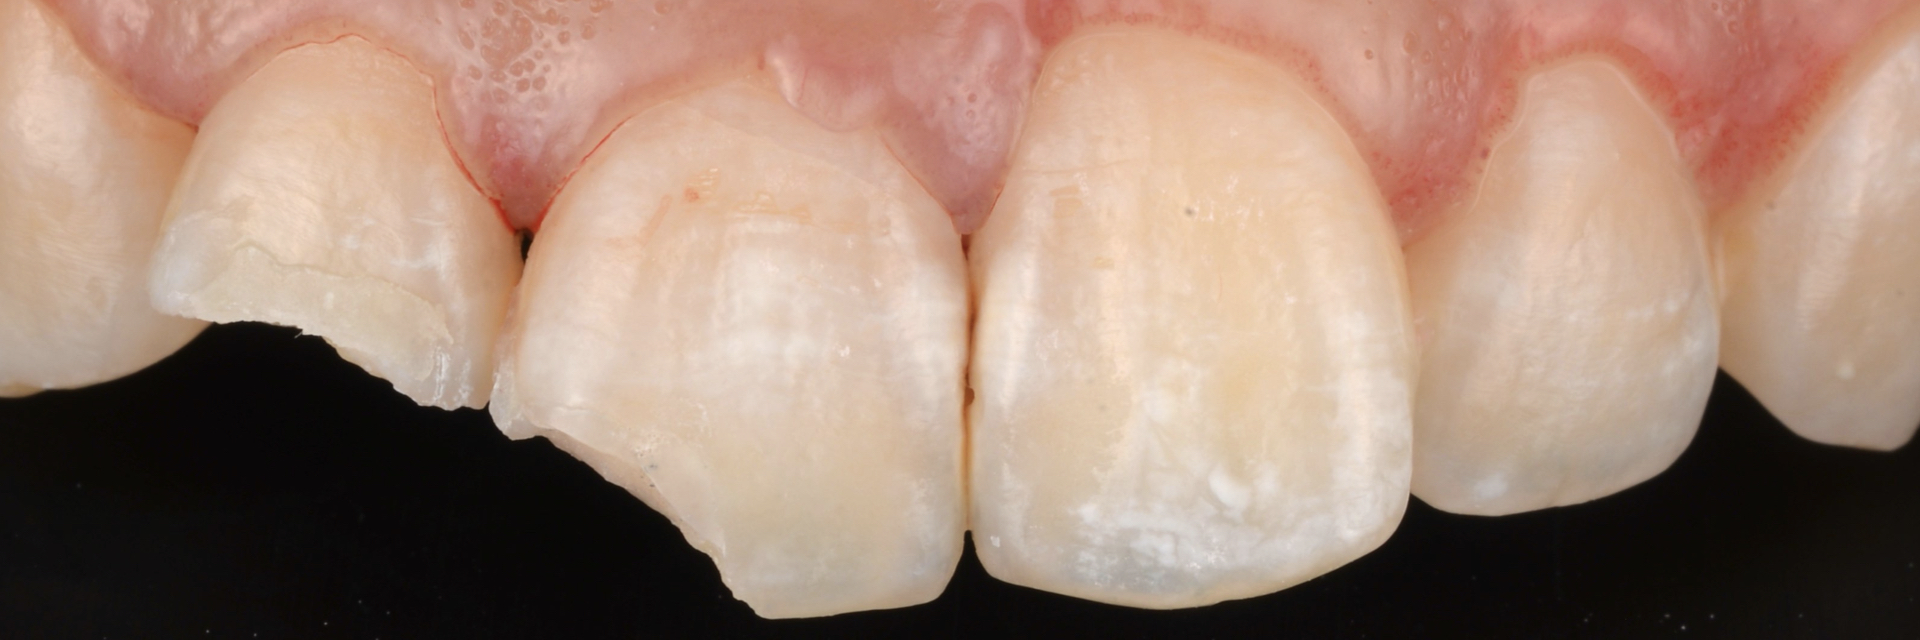

治療前

治療後